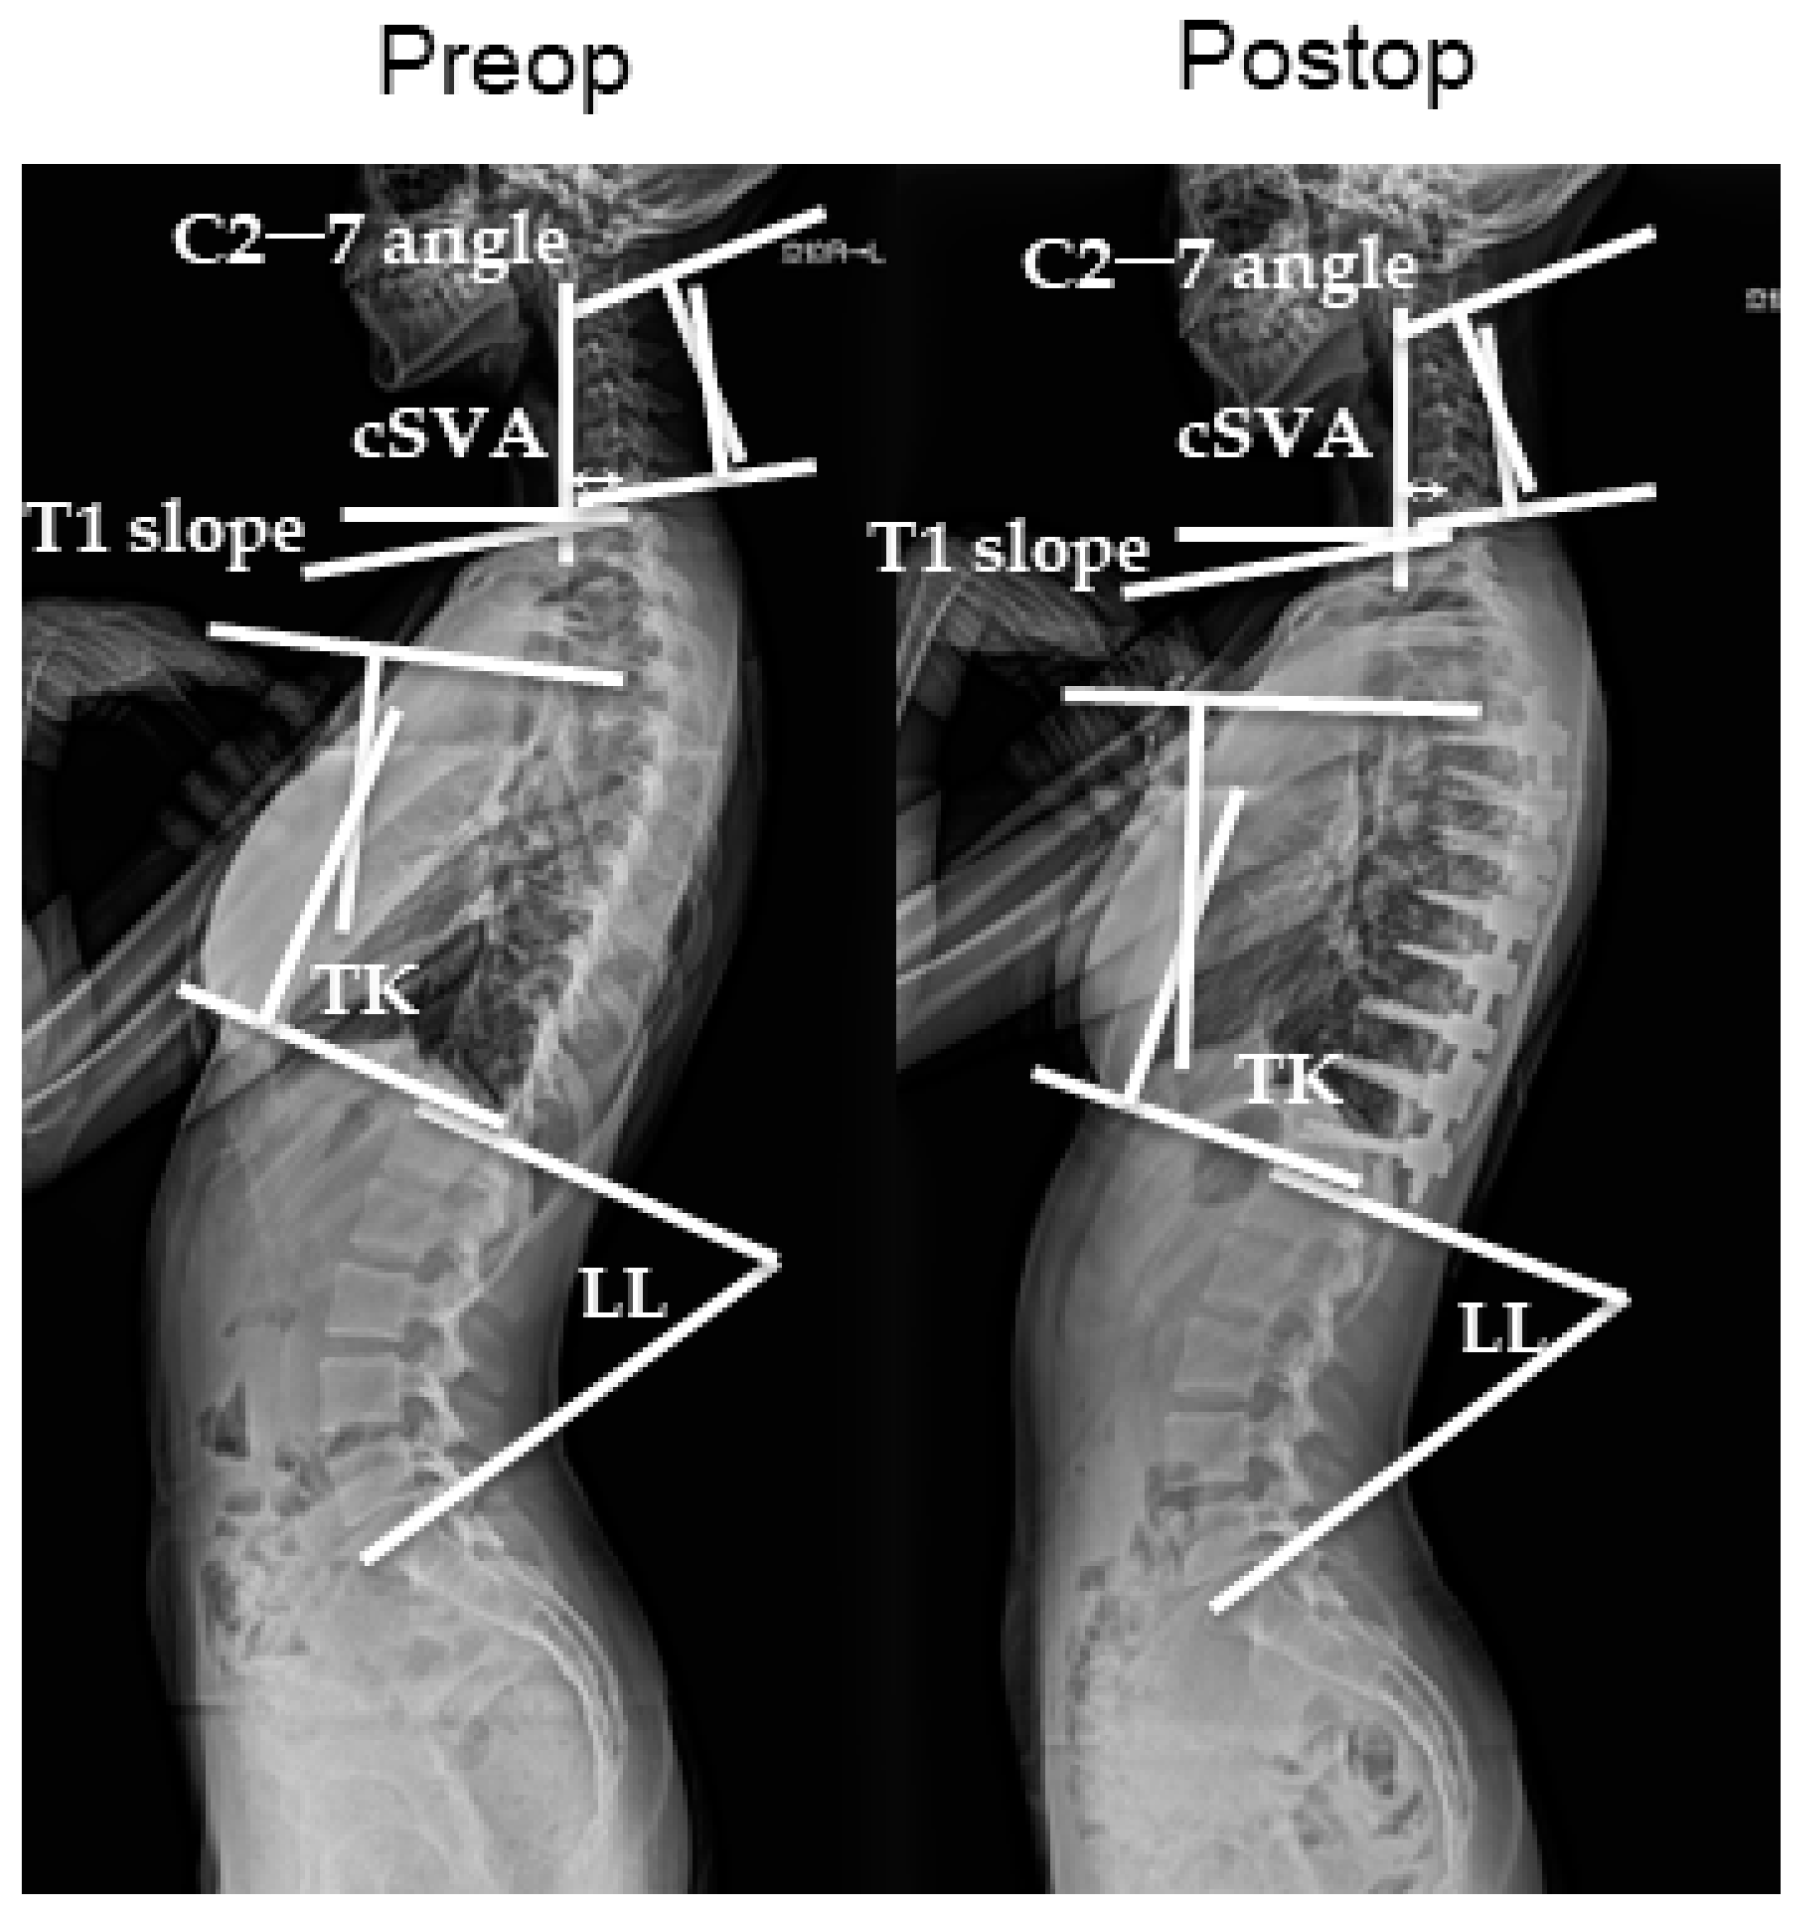

All patients underwent radiological evaluation of the whole spine before, immediately after, and at 1 year after surgery. Anterior and lateral radiographic images of the whole spine were obtained in the standing position. On the lateral view, the patients stood with the knees locked, feet shoulder-width apart, elbows bent, and finger joints in the supraclavicular fossa on each side and looked straight ahead. The Cobb angles were measured using the previously mentioned whole-spine radiographic images. The major curves were measured with the Lenke classification system. Using the same images, the sagittal alignment of the cervical spine was assessed using the following parameters: sagittal C2–C7 angles, segmental angles, and C2–7 SVA (sagittal vertical axis), which is the distance between the center of the C2 vertebral body and the posterosuperior corner of the C7 upper-end plate. Global cervical curvature (C2–C7 angle) and segmental angles were measured using the Harrison posterior tangent method. The sagittal C2–7 angle is measured with positive values indicating lordosis and negative values indicating kyphosis. T5–12 thoracic kyphosis (TK) and lumbar lordosis (LL) were also measured (Figure 1). All data were expressed as mean ± standard error of three independent measurements. Categorical variables were expressed as percentages. Radiographic measurements were obtained by two board-certified spinal surgeons (KM and TO).

Figure 1.

Standing lateral X-ray showing the calculation scheme before and after surgery.